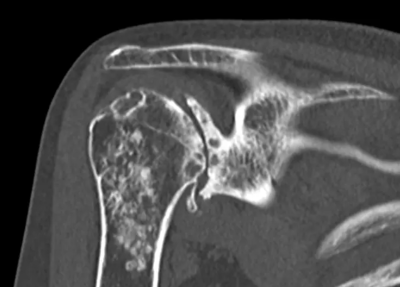

CT scan six years after surgery

Will the transplanted bone be maintained over time?

- We will show you the course over six years after surgery.